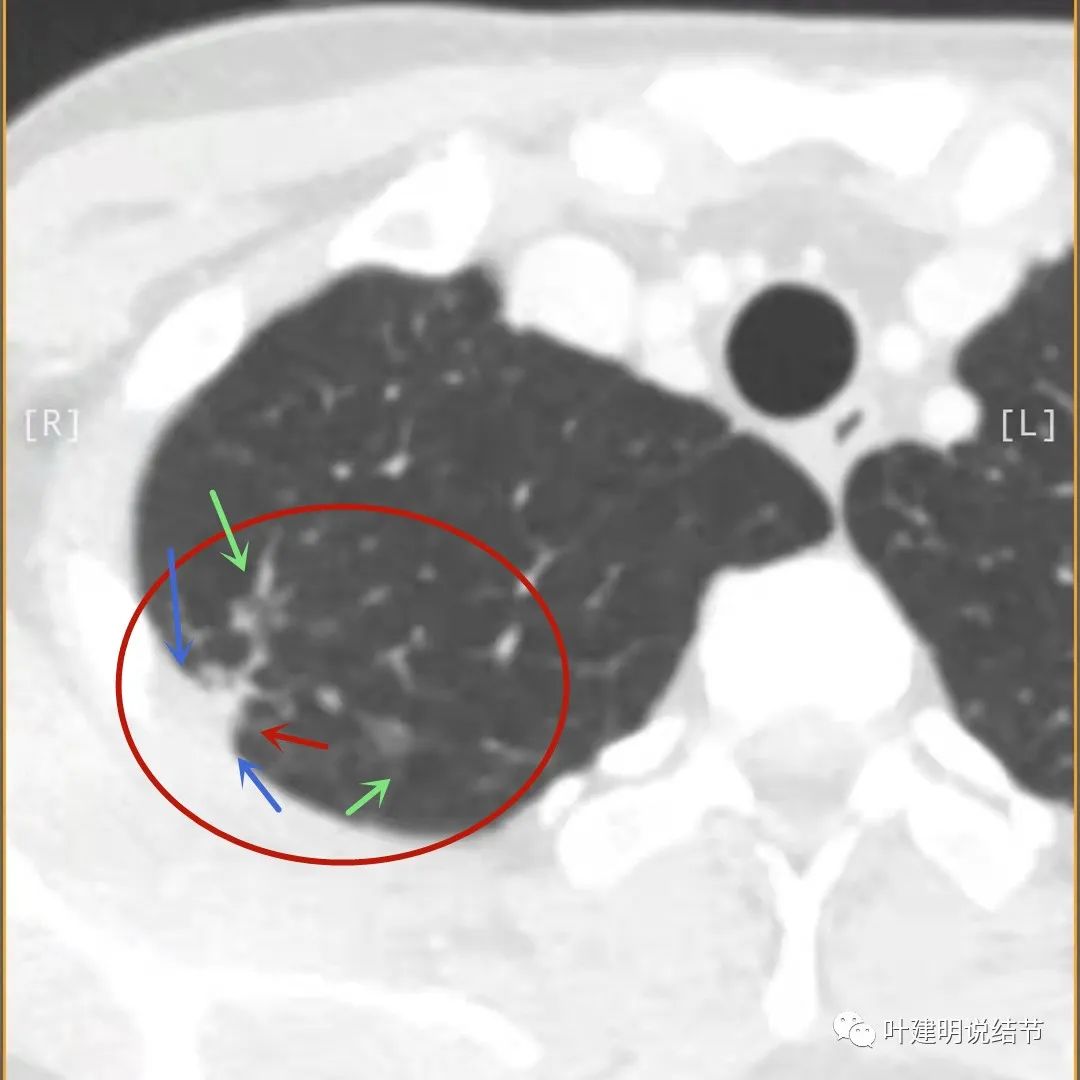

主病灶此层面似三角形,邻近胸膜增厚(蓝色箭头),结节实性部分密度较高(粉色箭头),边缘显模糊(砖色箭头)

上图与恶性较为符合,空洞性病灶,壁厚薄不均,增厚部分还凹凸不平(细红色箭头所指)

上图磨玻璃部分密度过低,且与正常肺组织界限模糊(砖色箭头),粉色箭头示囊壁密度过高的点状,蓝色箭头示邻近胸膜处的增厚

上图也像恶性,但整个囊壁的密度感觉过高了点,边缘磨玻璃淡、散且模糊,邻近胸膜有增厚

上图病灶的边相对比较光,没有毛刺征,邻近胸膜增厚

上图病灶边缘比较平直,没有膨胀性(桔色箭头),旁边的磨玻璃影淡且界限不清,邻近胸膜增厚。

再看影像印象:病灶较1年前有所进展,部分层面像恶性,囊壁厚薄不均,内面有小突起。但邻近胸膜增厚,旁边的磨玻璃部分散且淡,边界不清,实性部分边相对较光,囊壁有点状过高密度。良性可能性大些,恶性不能除外。